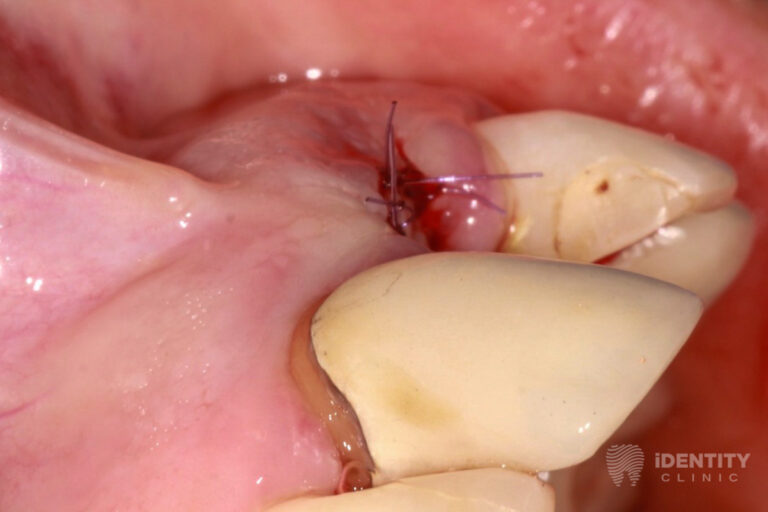

Reménytelen prognózisú 21 (bal felső első) fog eltávolítását követően a nagymértékű csonthiány miatt azonnali csontpótlást végeztünk a páciens saját csontja, illetve kötőszövete segítségével (alveolus prezerváció). Ennek 4 hónapos gyógyulási idejére az eltávolított 21 fog koronáját visszasíneztük a szomszédos fogakhoz. A teljeskörű parodontális terápiát mindeközben elvégeztük.

A gyógyulási időt követően implantátum beültetésével pótoltuk a 21 fogat, melyre az ezt követő 3 hónapos gyógyulási időre (az implantátum csontos gyógyulásának ideje) ideiglenes koronával láttunk el, mely már nagymértékben javította a páciens esztétikai kívánságát.

A bal felső első fog eltávolításával egyidőben csontpótlást (alveolus prezercációt) végeztünk. A sebészi beavatkozás lényege, hogy a fogeltávolítást követően az alveolus (az eltávolított fog helye a csontban) ne essen össze a nagymértékű csonthiány miatt, hanem azt fenntartva a páciens saját csontját és kötőszövetét felhasználva megőrizzük a csontkontúr eredeti formáját.